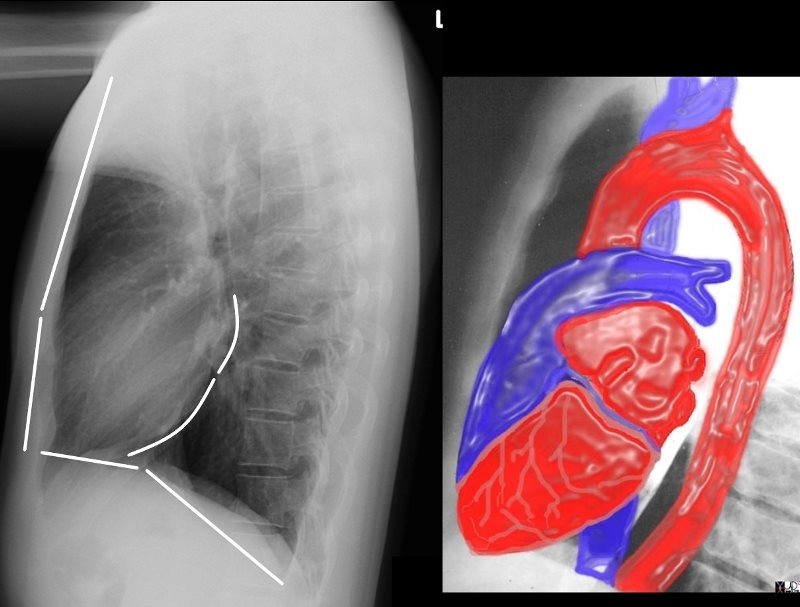

What is the most anterior structure of the heart

Hint chamber

RV,

Lateral chest x ray projection identifies RV dilation/hypertrophy by showing RV and it’s outflow track.

In a lateral chest x ray the coronary sinus is orientated _____ and located near the ______ aspect of the heart

orientated horizontally

near the posterior inferior aspect of the heart